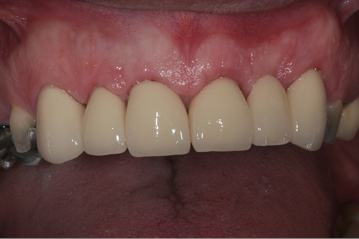

These are full crowns. Before shows old failing amalgam restorations.

- Tooth coloured porcelain with a metal lining, for strength and a good appearance

- Tooth coloured all – ceramic/porcelain, where the crown can be seen and the bite is not heavy